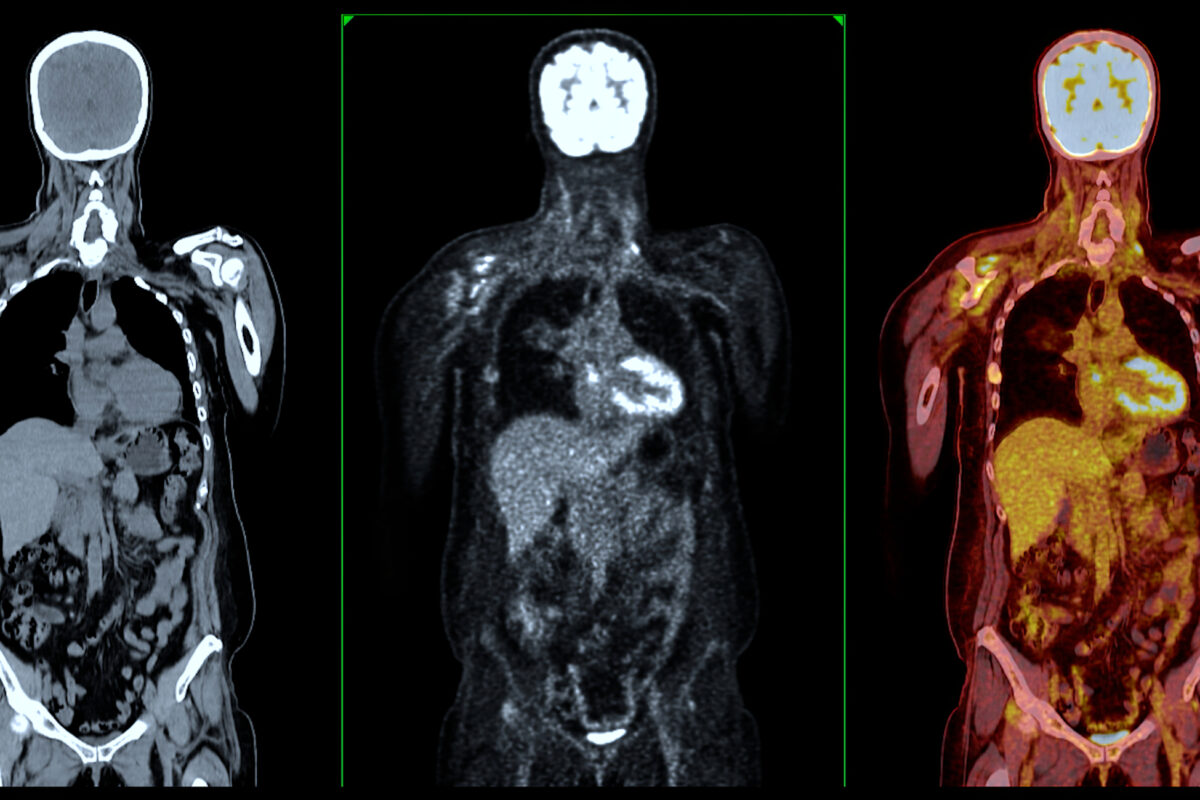

Medical imaging remains central to modern healthcare delivery. From radiography and ultrasound to MRI, PET-CT and hybrid molecular imaging systems, imaging technologies continue to transform diagnosis, treatment planning and disease monitoring.

Nuclear medicine and radiotheranostics are reshaping personalised care. Radiopharmaceutical innovation is accelerating. Quantitative imaging and advanced analytics are redefining how clinicians interpret complex disease.